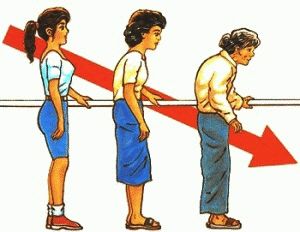

小贴士:目前在学术上有另外一种学说比较流行,骨质增生的本质是人体力学平衡失调的结果。保持人体生物力学的完整及正确性对预防骨质增生至关重要。

最后,骨质增生其实人体代偿的产物,当骨关节周围软组织的应力异常(正常生物力学改变)后,人体通过粘连、瘢痕、挛缩这些不能代偿对抗异常应力的情况下,软组织牵拉骨附着处引发硬化→钙化→骨化的病理过程引起骨质增生,通过骨质增生代偿的恢复人体生物力学平衡,就好比围墙老化了要倒了,我们在旁边代偿的增加修建一条支撑柱防止围墙倒塌。所以骨质增生既是生理性的,又可转为病理性的,如果增生的位置正好压迫神经、血管,则属于病理性的。应了开篇那句话"具体事物,具体分析“。

骨质增生不再是老年人的专属疾病,随着工作、生活方式的改变,脊柱骨质增生越来越多,越来越年轻化,尤其是只能手机、电脑的普及,在刷微博、刷朋友圈的过程中,低头族们的颈椎早就超出了自己承受范围,不可避免的引起骨质增生。对于骨质增生的治疗,最好的意见是:早发现;早预防;早诊断;早干预。